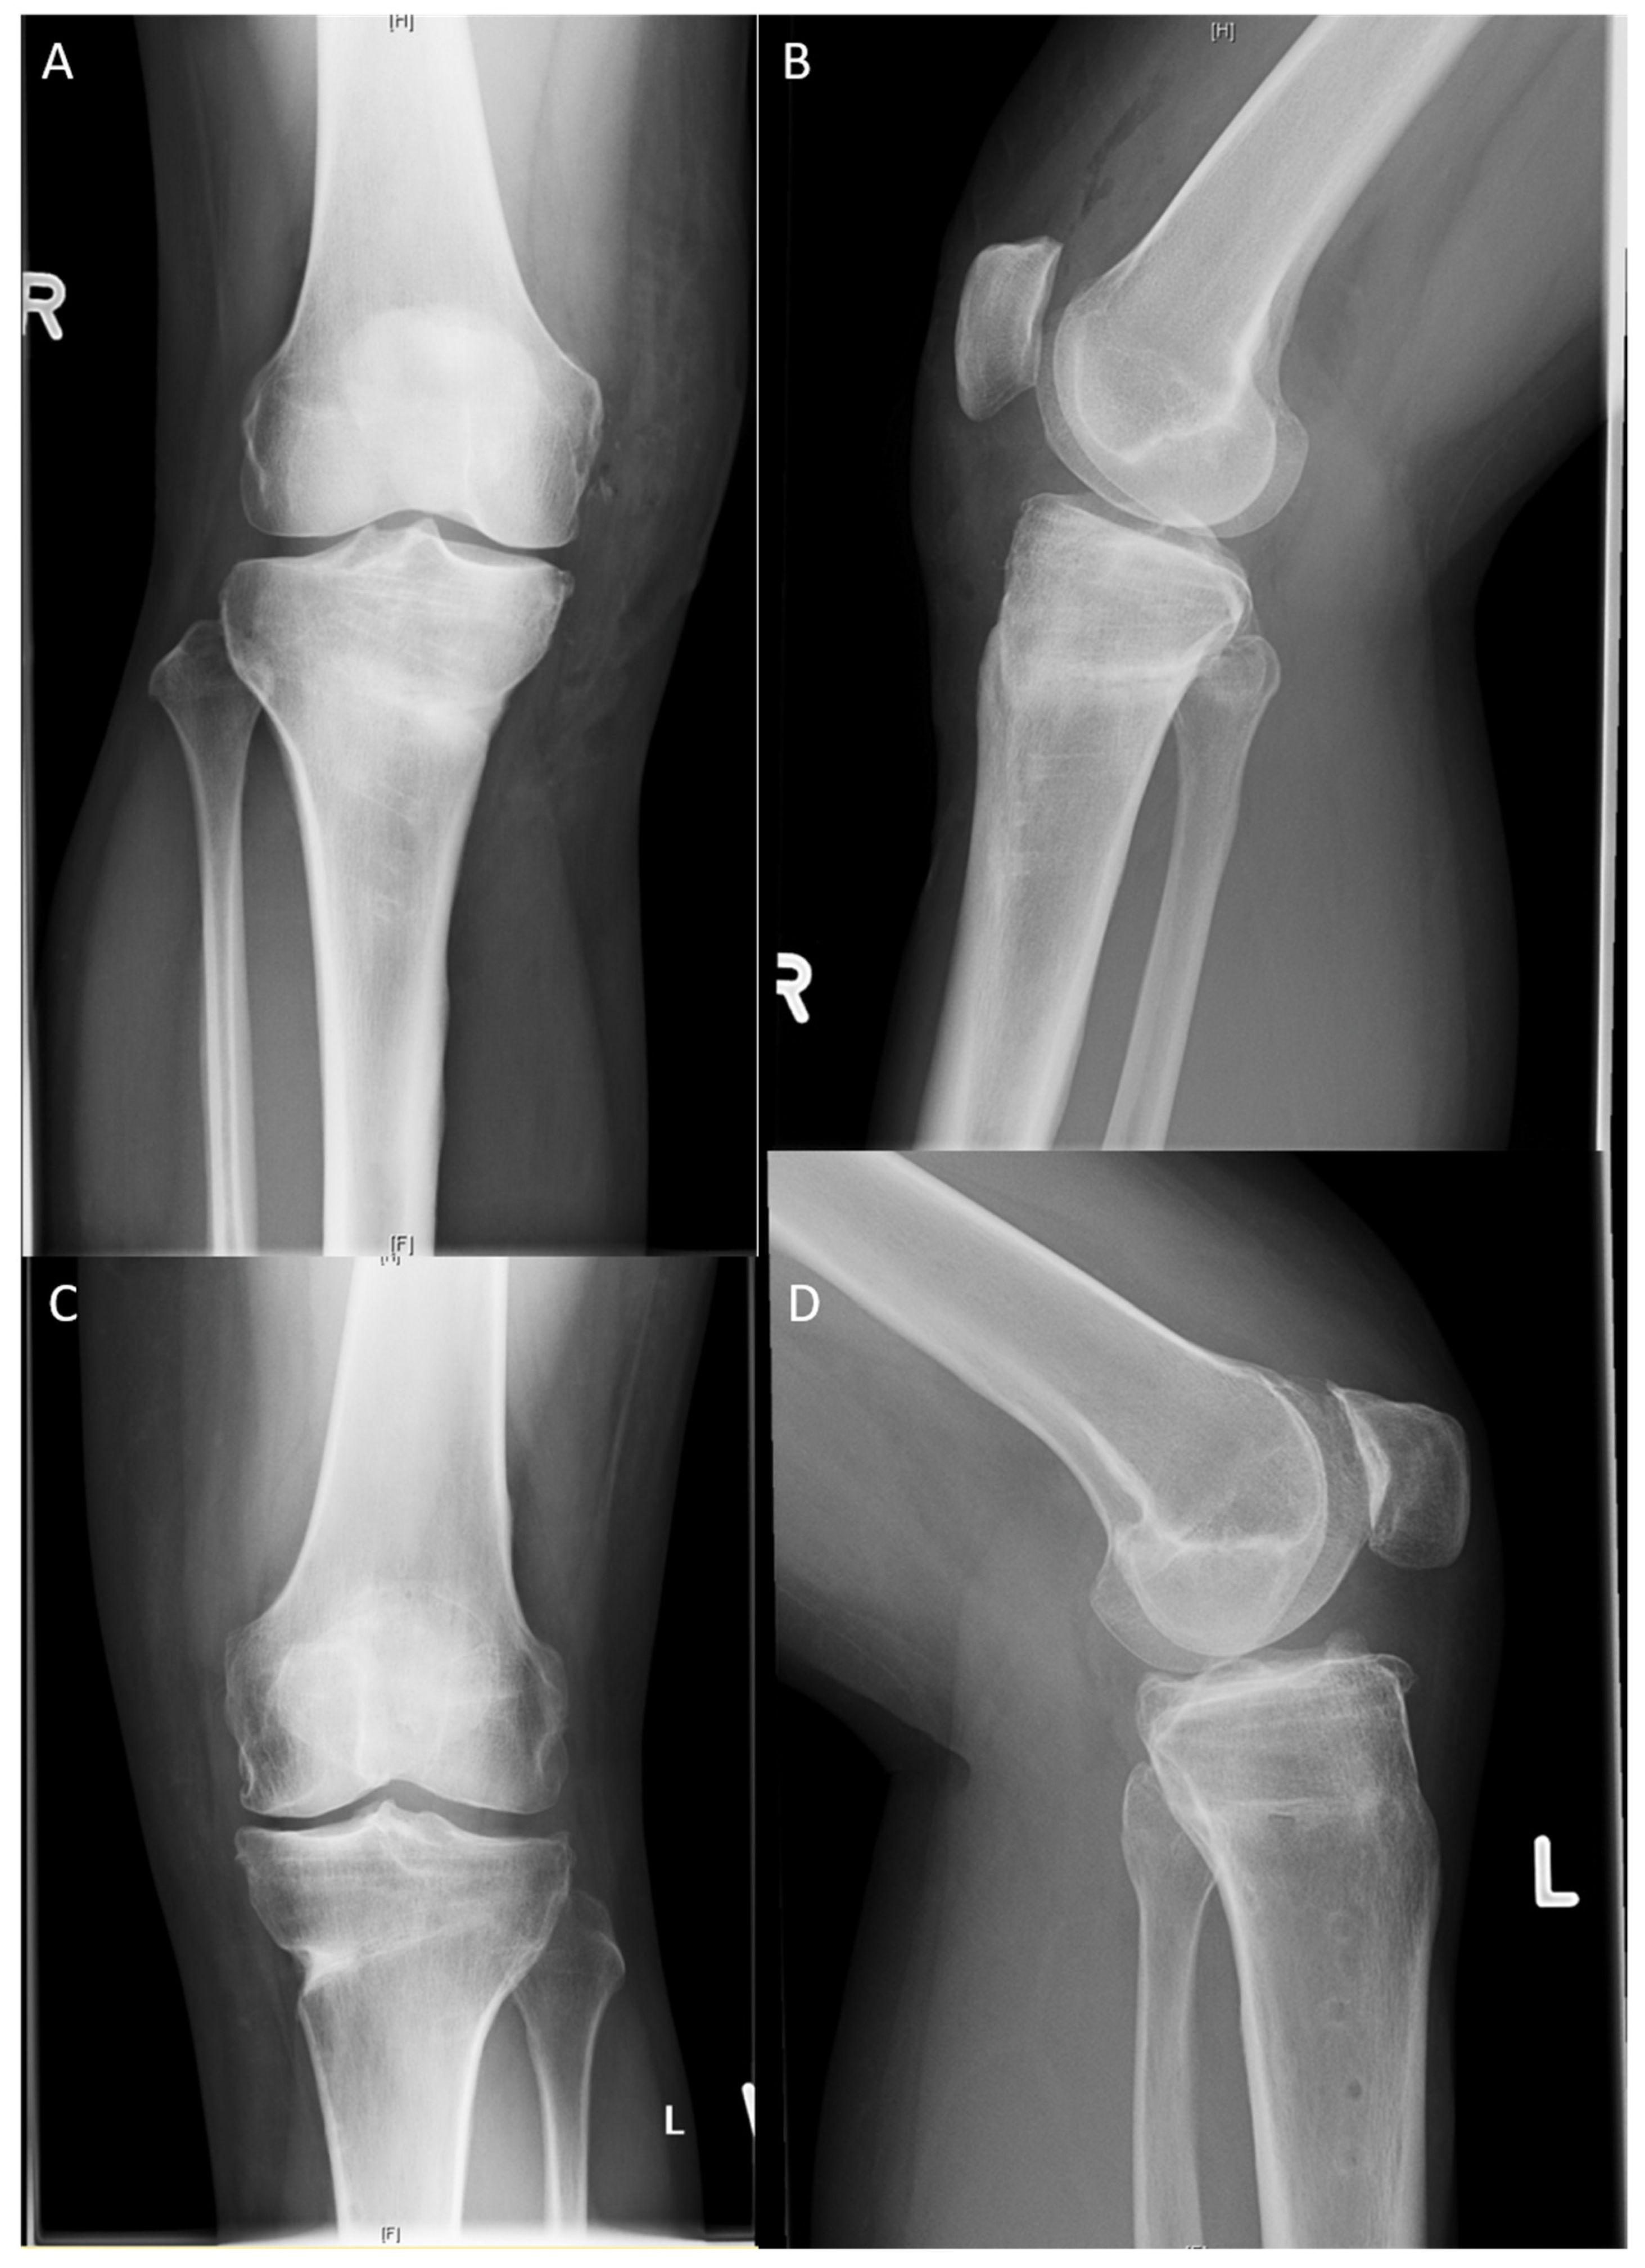

Figure 6.

Post-operative X-rays after implant removal: (A) LOQTEQ® HTO plate (aap Implants, Berlin), knee a.p.; (B) LOQTEQ® HTO plate (aap Implants, Berlin), knee lateral; (C) TomoFix™ plate (Synthes, Switzerland), knee a.p.; (D) TomoFix™ plate (Synthes, Switzerland), knee lateral.